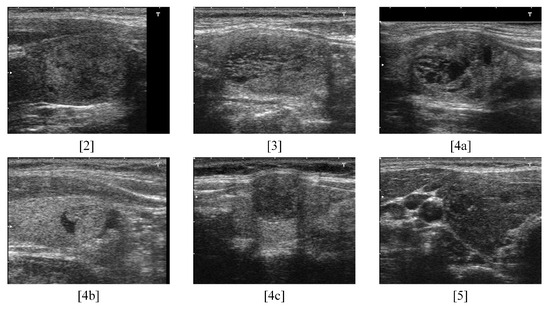

- [2] Benign (0% risk of malignancy);

- [3] No suspicious US feature (<5% malignancy);

- [4a] One suspicious US feature (5–10% malignancy);

- [4b] Two suspicious US features (10–80% malignancy);

- [4c] Three or four suspicious US features (10–80% malignancy);

- [5] Five suspicious features (>80% malignancy).